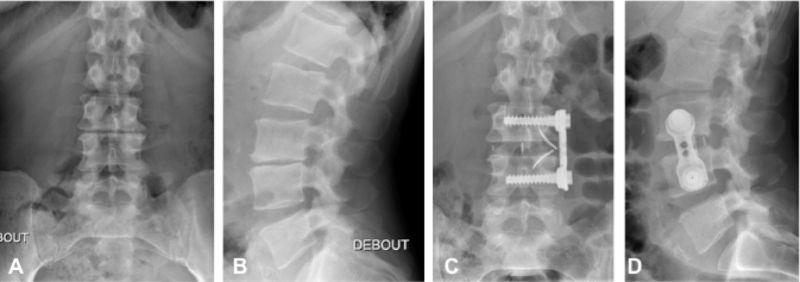

Arthrodese Lombaire Mini Invasive Par Voie Anterieure Doscea

Arthrodeses Lombaire Et Dorso Lombaire Post Espace Sante Cassis